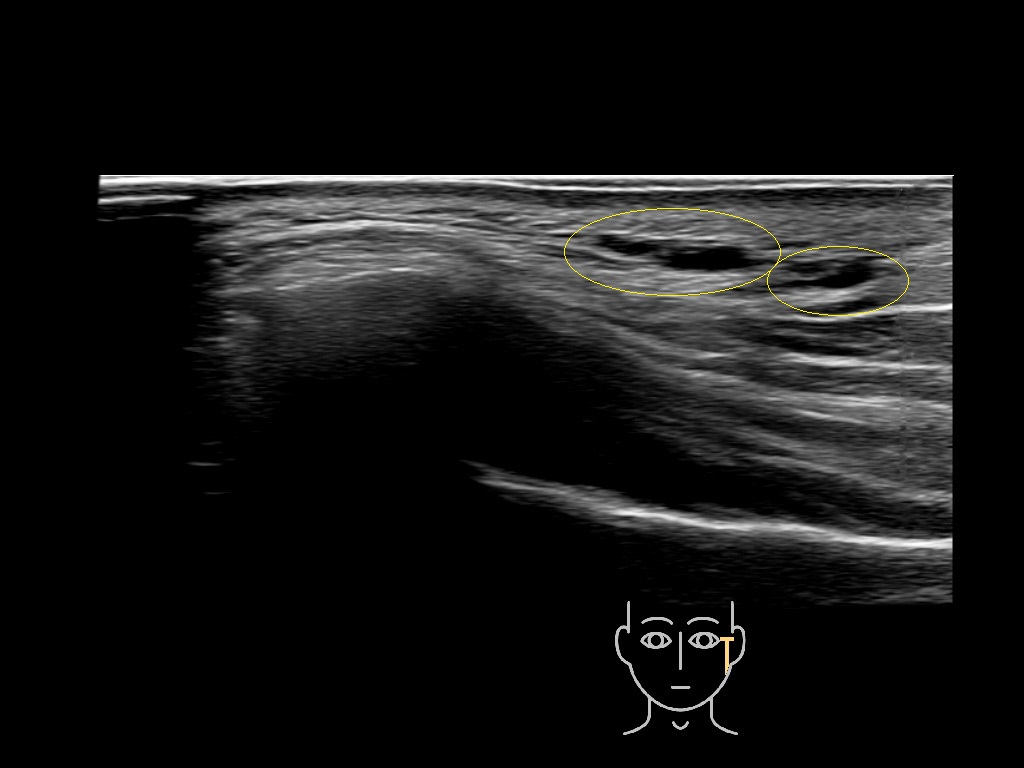

Filler deposits may end up unintentionally in the SMAS or fascial layers of the skin. Very often this will not lead to adverse events, however, adverse events ( nodules, migration / redistribution impaired muscle movement and smiling and malar edema) are are often related to filler ending up in the SMAS or fascia.

Study the first image to recognize the different layers. If you are sure about the layers, swipe to the second image to view the answer (if applicable).